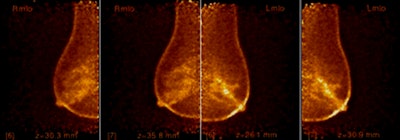

![]() |

| Slide courtesy of Bonnie Rush (images from Imaging Diagnostic Systems). |

But CTLM has some definite downsides, Rush said. Currently, it takes approximately 10 to 15 minutes to image each breast, even though the image reconstruction process occurs at the same time. In addition, data for the technology's sensitivity and specificity vary: In dense breasts, it beats mammography at 74.40% versus 34.4% for sensitivity, but comes in second for specificity at 72.2% versus mammography's 90.48%.